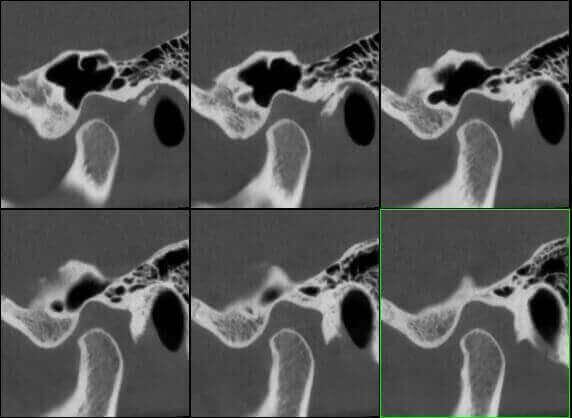

Impianto Cocleare